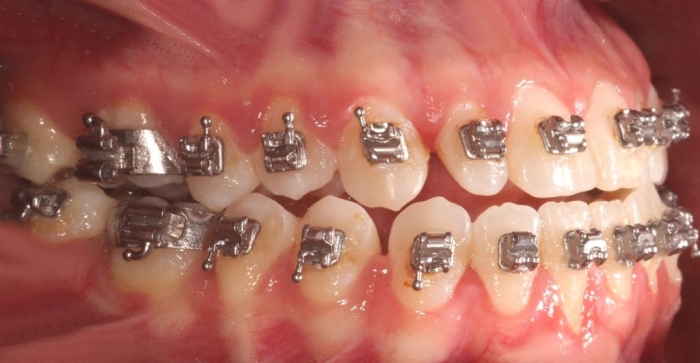

Mordida inicial - Clínica Cliniface

Mordida inicial